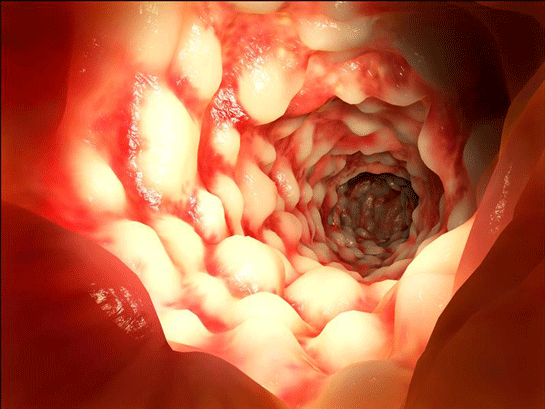

Rektal Korpus Rektal korpus, rektumun ana bölümüdür ve burada dışkı depolanır. Rektal korpus, rektumun en uzun bölümüdür ve iç yüzeyi, dışkının rahat bir şekilde depolanmasını sağlayan bir mukoza tabakası ile kaplıdır. Bu tabaka, çeşitli bezlerin ve mukus salgılayan hücrelerin varlığı sayesinde, dışkının kayganlığını artırarak dışkılama sürecini kolaylaştırır. Rektal Ampul Rektal ampul, rektumun alt kısmında yer alır ve dışkının depolandığı ana alan olarak işlev görür. Bu bölümde, dışkı miktarı arttıkça rektal ampul genişler ve bu genişleme, kişinin dışkılama ihtiyacını hissetmesini sağlar. Rektal ampul, ayrıca çeşitli sinir uçları ve reseptörler içerir, bu sayede rektumun doluluğu hakkında beyne sinyaller gönderilir. Anüs Anüs, rektumun son kısmıdır ve vücut dışına açılan bir açıklık olarak görev yapar. Anüs, iç ve dış anüs kasları ile çevrilidir. Bu kaslar, dışkılama esnasında kontrol mekanizması sağlar ve anüsün kapanmasını sağlar. Anüsün iç kısmında yer alan iç anüs kası, istemsiz olarak çalışan bir kas iken, dış anüs kası, istemli olarak kontrol edilebilir. Rektumun Fonksiyonları Rektumun başlıca fonksiyonları şunlardır:

Dentat çizgi, rektumun üst kısmında bulunan ve anal kanaldan ayrılan bir yapı olarak tanımlanabilir. Bu çizgi, rektumun iç yüzeyinde yer alan ve ince bağırsak ile anüs arasında bir sınır oluşturan belirgin bir çizgidir.

Dentat çizgi, rektumun yaklaşık 2-3 cm kadar üst kısmında yer alır. Bu çizgi, rektumun iç yüzeyindeki epitel hücrelerinin değişimi ile belirginleşir; yukarıda yer alan rektum bölgesinde silindirik epitel bulunurken, aşağıda yer alan anal kanalda ise çok katmanlı yassı epitel bulunur.